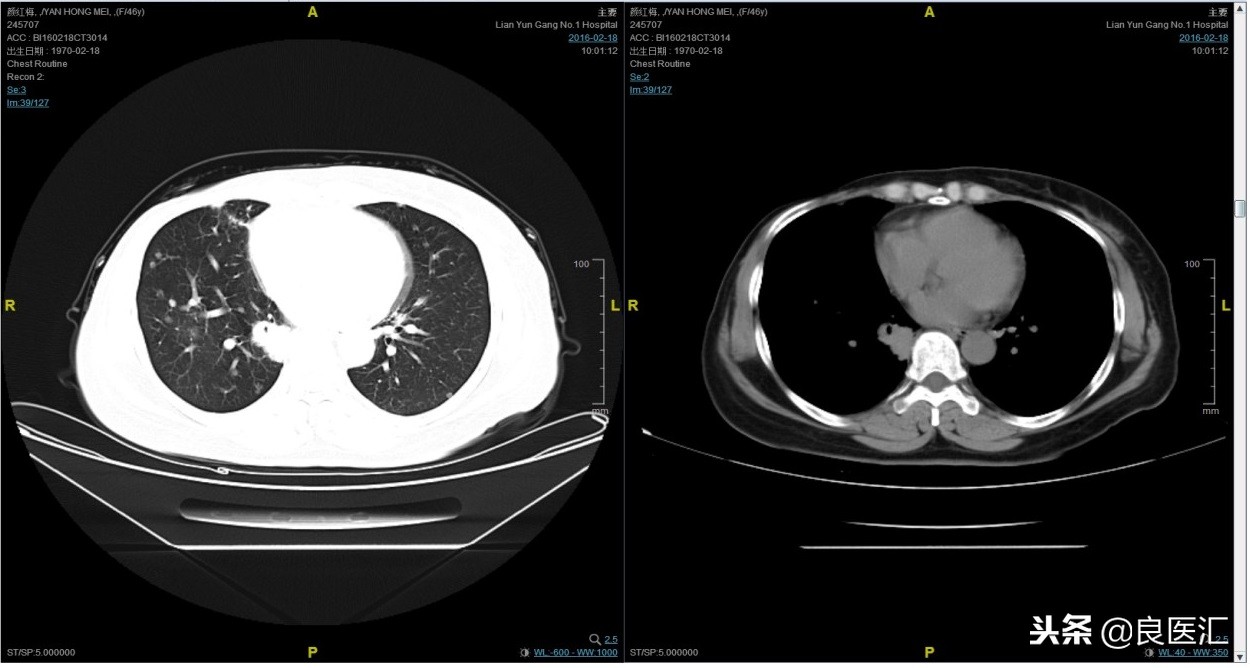

随访至2016-2-18,肺部病灶进展,肺内转移病灶增多。PFS2=10个月。

从2016-2-19开始给予紫杉醇+曲妥珠单抗治疗,紫杉醇240mg,3周重复,曲妥珠单抗330mg三周重复。患者末次应用曲妥珠单抗和紫杉醇时间为2016-6-24,紫杉醇共应用4周期。

期间2016-4-22复查CT如下:

2016-7-5化疗结束后复查CT,疗效评价稳定。